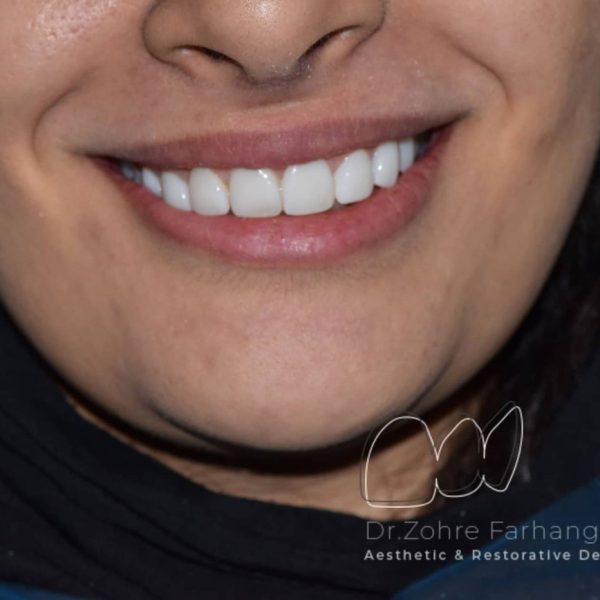

نمونه کار شماره ۱۹ کامپوزیت ونیر

کامپوزیت ونیر دندانهای فک بالا و پایین

مراحل درمان به شرح زیر:

۱.حذف ونیرکامپوزیتهای معیوب قبلی

۲.اصلاح ناقرینگی لثه دردندانهای قدامی(لیفت لثه)

۳.کامپوزیت ونیر دندانهای فک بالا و پایین

به کامپوزیتهای قبلی بیماردقت کنید که فاقد هرگونه آناتومی و ظرافت بوده و قوس لبخند کاملا به شکل یک خط صاف و غیر اصولی بوده، درست انتخاب کنید و یک مسیر را چند بار نروید😊